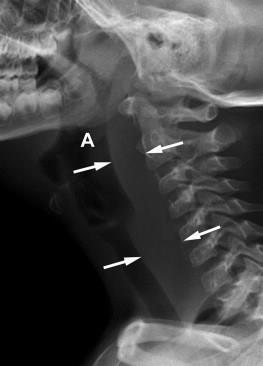

경동맥 등과의 위치 관계에 따라 접근하기 쉬운지를 보고 구강 내로 접근하여 배농할지 목 바깥쪽을 절개하여 접근할지 결정합니다.인두후농양 인두후공간은 척추의 전근막과 목의 후방부인 인두벽근막과 식도 사이의 공간입니다. 인두 후 농양은 일측성으로 발생하며 종격동에까지 염증이 파급되는 중요한 경우가 됩니다. 2세 이하의 소아에게 흔히 발생하며, 발열, 연하장애, 발성장애, 침, 호흡곤란이나 경부경직 등을 호소하게 됩니다. 신체 검사를 통해서는 한쪽 인두 후벽 종창을 관찰할 수 있습니다. 그러나 이와 같은 전형적인 증상은 소아의 10% 미만에서 관찰이 됩니다. 일반 소아에게 흔히 있는 합병증이므로 방사선 검사상의 협조가 어렵고 CT 등으로 진단하게 됩니다. 역시 마찬가지로 입원 및 수술적 치료를 주로 하지만, 주로 경구절개로 배농을 하지만 농양이 너무 아래로 내려간 경우에는 경부접근으로 수술이 이루어집니다.

인두 후 농양은 드물지만 x선 상에서도 기도 후방부 연조직 음영이 증가한 경우 의심해 볼 수 있습니다.비화농성 합병증으로 고름이 쌓이는 합병증이 아니라 전신 질환과 관계가 있다는 생각입니다.상기도와 편도, 치아를 포함한 구강은 항상 세균에 누출되어 있기 때문에 표면 항원성의 변화가 일어날 수 있습니다. 표면 항원성이 바뀌면 면역 감시 시스템이 자극을 받아 자가 항체가 생산됩니다. 편도선에서 생성된 자가 항체는 혈관으로 들어가 체순환계를 통해 신체 각 부위를 순환하고 원격부위의 표면항원에 침착하게 항원항체 반응을 일으킵니다. 이 경우 조직손상이 발생하여 2차질환이 발생합니다. 한편 세포매개성 면역반응으로 인해 한쪽 표면의 변형된 상피항원에 의해 감작된 림프구가 세포독성으로 인해 원격부위에서 2차 질환을 일으킬 수 있습니다. 이러한 만성이든 급성이든 염증이 있는 편도로 인해 피부, 관철, 뼈, 신장 등의 2차 질환을 유발합니다.